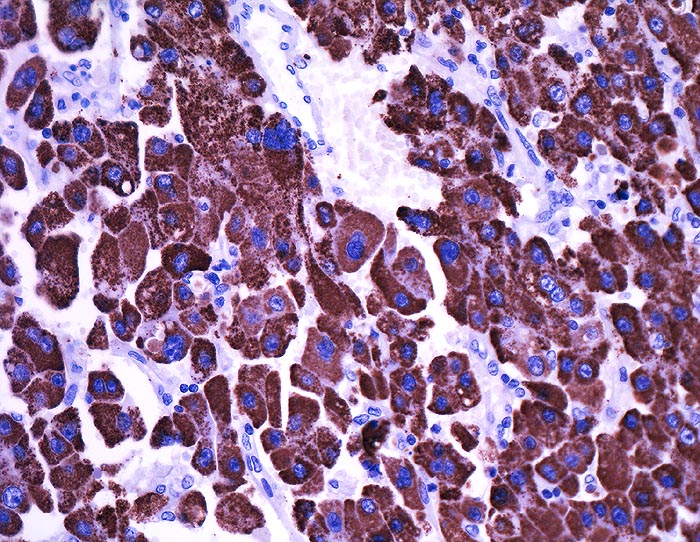

Hepatozelluläres Karzinom : Ovarmetastase

Die hepatozytenähnlichen Anteile der Metastase reagieren sehr stark mit dem hepatozellulären Marker Hep-Par1

St.n. Lebertransplantation wegen Hepatozellulärem Karzinom bei Hepatitis C vor 2 Jahren. Jetzt Metastasen von 12 und 14cm Durchmesser in beiden Ovarien.

Histologie

Immunhistochemie

Hep-Par 1, Hepatocyte